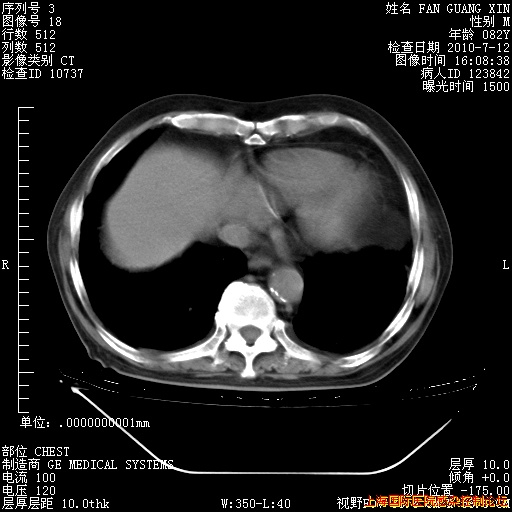

6月12日纵膈窗

回复